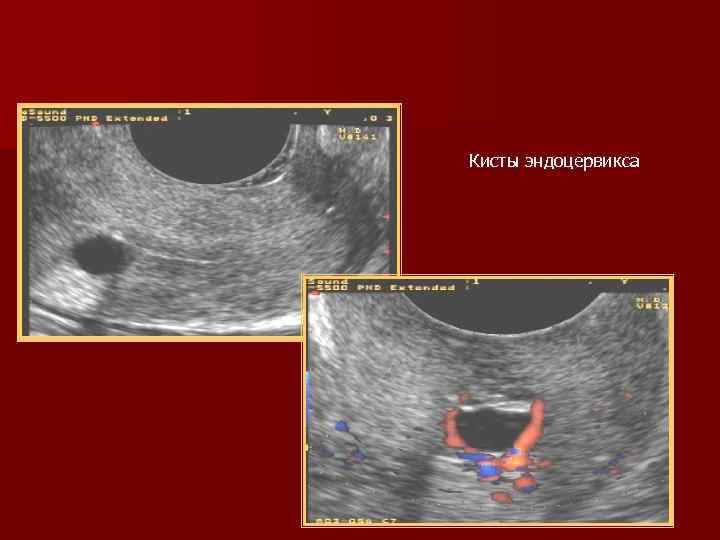

Кисты эндоцервикса